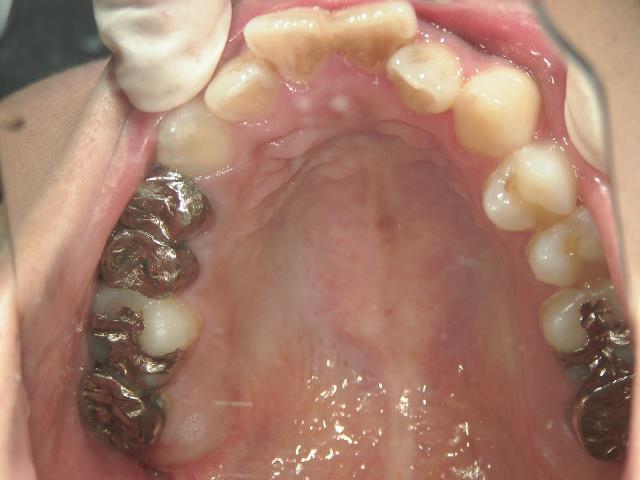

矯正歯科 治療前 上顎を装置(QH)で拡大後ワイヤー矯正へ移行、右下5番左下4番 計2本抜歯叢生改善

矯正_灰色.pngno.28_6958_治療前_上.jpg矯正_灰色.png